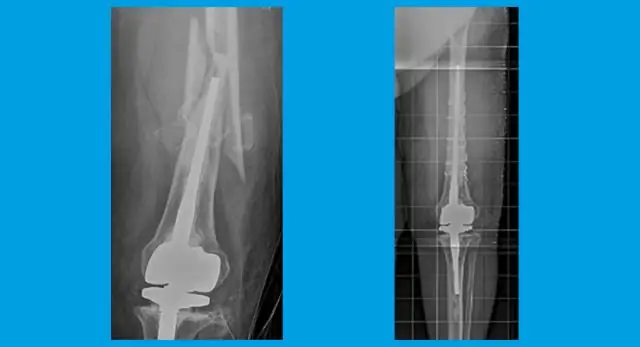

Дисплазия большеберцовой кости. Дисплазия большеберцовой кости включает чрезмерный изгиб или искривление большеберцовая кость (также называемая костью голени). Если дисплазия большеберцовой кости Если есть подозрение и подтверждение на рентгеновском снимке, ребенка следует направить к ортопеду для лечения, направленного на профилактику и лечение переломов.